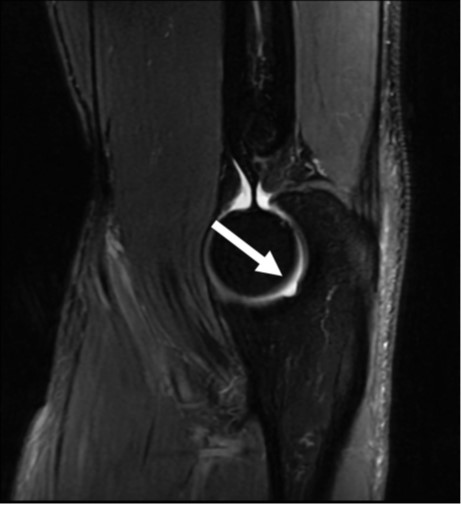

The capitellum is a hemispherical protuberance along the anterior and lateral aspects of the distal humerus. The anterior 180° of the capitellum is round, smooth, and covered by articular cartilage. As the capitellum curves distally and posteriorly, it tapers in width. The posterolateral aspect of the capitellum is devoid of articular cartilage and often has a rough and irregular appearance. A groove is normally present between the posterolateral aspect of the capitellum and the lateral epicondyle [3, 4].

The abrupt change in contour of the articular capitellum at the junction with the lateral epicondyle can create a pseudodefect of the capitellum on coronal MR images. This finding is more pronounced in contrast to the smooth articular surface of the radial head or in the presence of a joint effusion where fluid outlines the groove. The pseudodefect can simulate an osteochondral lesion, particularly when there is accompanying fibrocystic change. However, the two can easily be distinguished by their anatomic location on sagittal images: the pseudodefect will be along the posterior nonarticular surface of the capitellum (Fig. 3), whereas an osteochondral lesion will be located along the anterior capitellum and is commonly accompanied by subchondral cystic change, bone marrow edema, and a joint effusion [1–4].